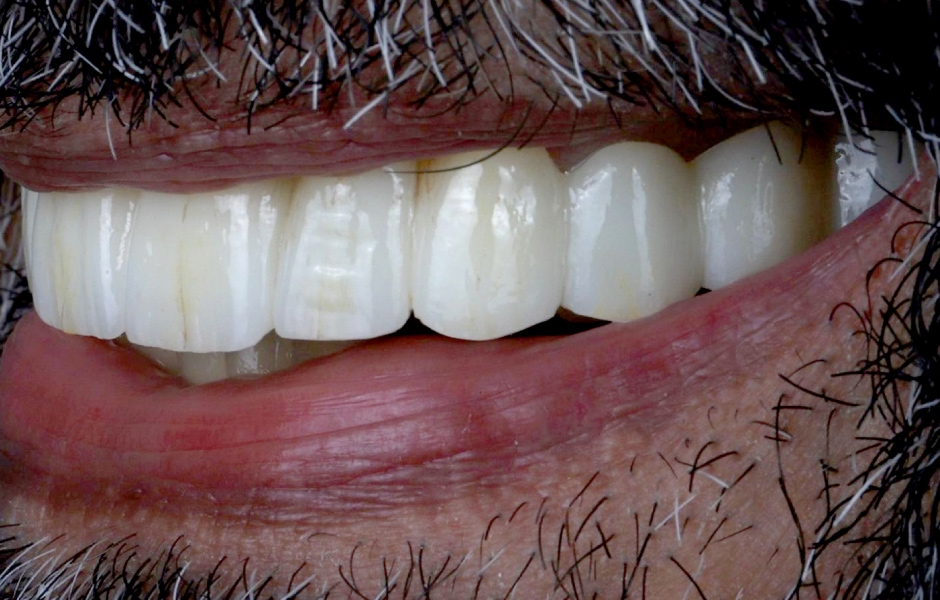

Definitivní náhrada byla nasazena a ověřena z hlediska estetiky, okluze a funkce (obr. 51–55). Panoramatický kontrolní snímek potvrdil, že všechny parametry protetického ošetření odpovídají očekávaným hodnotám (obr. 56).

Při kontrole po 18 měsících po dokončení ošetření bylo provedeno intraorální, extraorální a radiografické vyšetření. Nebyly zjištěny žádné patologické nálezy a výsledné parametry zůstaly stabilní (obr. 57–62).

Obr. 51

Obr. 52

Obr. 53

Obr. 54

Obr. 55